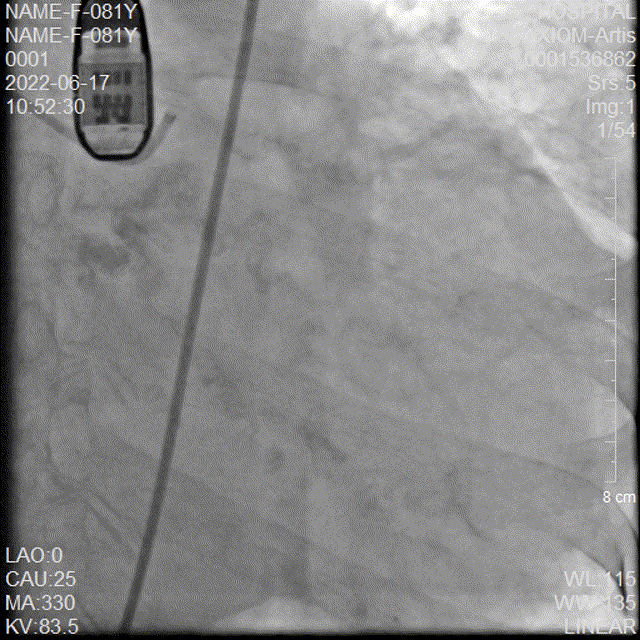

20mm球囊后扩

后扩后造影

本例手术为Type1型二叶式主动脉瓣重度狭窄合并中量返流的高龄心衰患者,重度钙化且分布不均匀,右冠窦内钙化向左室流出道衍生,左室流出道呈敞口形态,术中瓣膜释放过程中多次出现下滑,黎文生教授TAVR团队通力配合、全面细致评估,充分利用TaurusElite瓣膜系统优异的多次可回收功能,在瓣膜释放至工作位时多角度评估瓣膜植入深度、锚定力以及冠脉灌注情况,最后瓣膜释放定位位置接近瓣环。为使患者获益更佳,决定使用20mm球囊后扩改善瓣膜展开形态及组织贴合情况。

术后行主动脉根部造影检查与经食道超声影像评估,无瓣周漏,瓣膜形态良好,跨瓣压差由术前的107 mmHg即刻下降为0 mmHg,TaurusElite植入圆满成功!